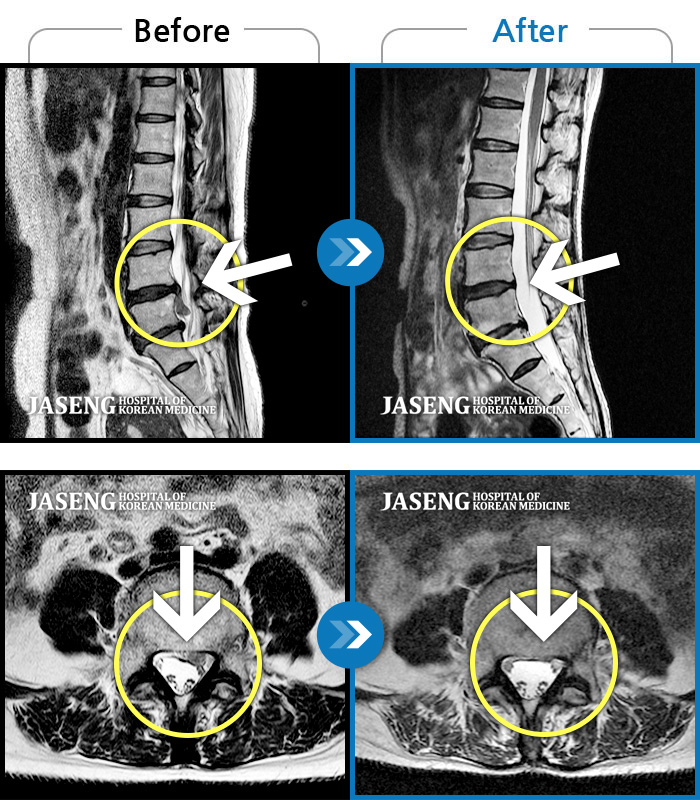

허리디스크

대전 · 김창연 원장

허리랑 좌측 엉덩이가 뻐근하게 많이 아프고, 허벅지와 종아리가 저림이 심해요. 걷기가 힘들어요.

촬영시기

2023.10.30 ~ 2024.07.19

2024.08.09